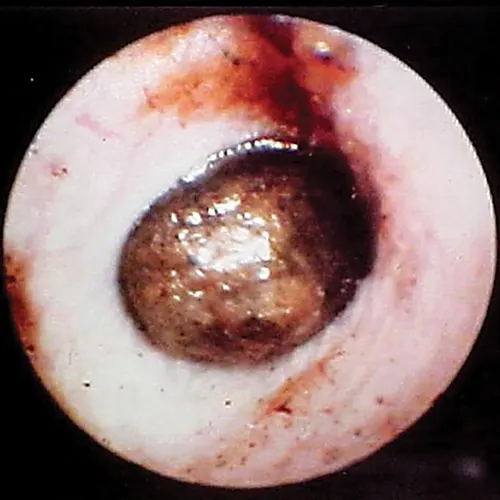

Ulceration of the ear canal epithelium is most often associated with a severe, chronic bacterial otitis externa (often Pseudomonas spp). The bacteria releases cytopathic enzymes resulting in ulceration (Figure 6). Tumors within the ear canal may be present and should be noted (Figure 7).

selected slide image

FIGURE 6

1 / 5

Ulceration of the ear canal. Note the disruption of the surface epithelium.